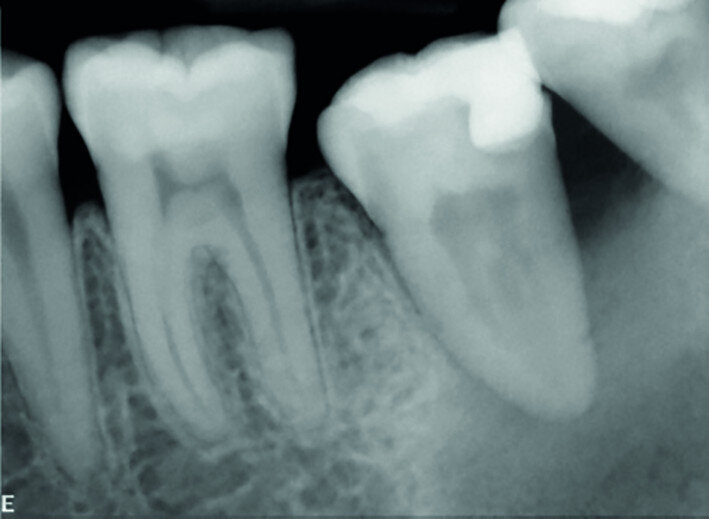

Fig. 3: Pre-op periapical radiograph.

A 47-year-old male patient in a good medical condition and a non-smoker was referred to our dental practice for endodontic retreatment of the right maxillary second molar. The dental history revealed that the tooth had been endodontically treated three months before because of acute pulpitis. After the treatment, the patient complained of pain on chewing. Antibiotics and a non-steroidal anti-inflammatory drug were prescribed, but the pain remained. After a month, a sinus tract appeared. The tooth was retreated in another practice without success. The clinical inspection revealed the presence of a sinus tract near the apical region of tooth #17. The tooth had been prepared for a full crown, but was without even a temporary crown, and the access cavity had been closed with temporary filling material. Cracks were evident on the buccal and mesial surfaces. Periodontal probing showed a deep pocket (> 12 mm) on the distal aspect of the root trunk (Figs. 1 & 2). The periapical radiograph showed a radiolucency between the roots of the second and third molars. The radiographic appearance of the endodontic treatment was good, without clear evidence of periapical radiolucencies (Fig. 3). A perforation of the pulp chamber floor was suspected. A CBCT scan was performed (Figs. 4–7), and it confirmed the suspicion of perforation, along with the presence of a large periradicular radiolucency and an unfavourable root shape.